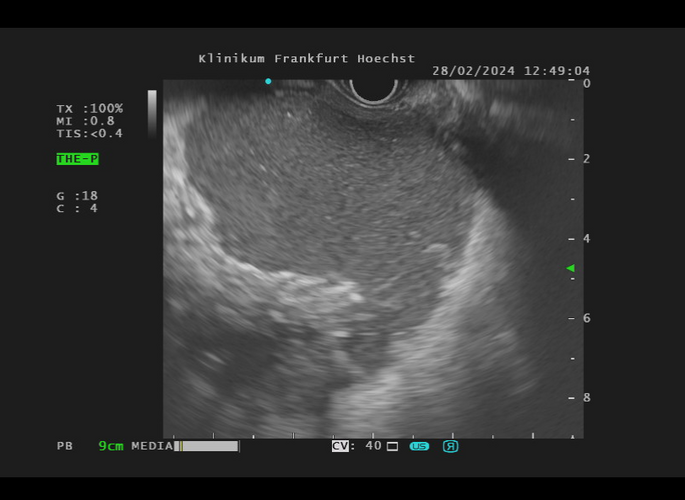

Die Endosonographie ermöglicht eine sehr schonende Diagnostik und Therapie an den Bauchorganen. Im Vergleich zu anderen bildgebenden Verfahren wie der Abdomensonographie, der Computertomographie (CT) oder der Magnetresonanztomographie (MRT) bietet nur die Endosonographie den Blick von innen auf die Organe. Die Speiseröhre (Ösophagus), Magen, Zwölffingerdarm (Duodenum), Bauchspeicheldrüse (Pankreas), Gallenwege, Gallenblase und Enddarm (Rektum) liegen besonders im Fokus der Endosonographie.

Die Untersuchung wird in der Regel unter Sedierung, also mit einer Schlafspritze, durchgeführt, wie man es von der Magen- oder Darmspiegelung her kennt. Wo noch vor wenigen Jahren häufig eine Operation notwendig wurde, kann heute die endosonographische Therapie weiterhelfen. Beispiele hierfür sind die Ableitung von Flüssigkeitsverhalten nach innen und die Abtragung von entzündlichem oder untergegangenem Gewebe (endosonographische Drainage, Pankreatikogastrostomie, Choledochoduodenostomie, endoskopische Nekrosektomie, endosonographische Stenteinlage).